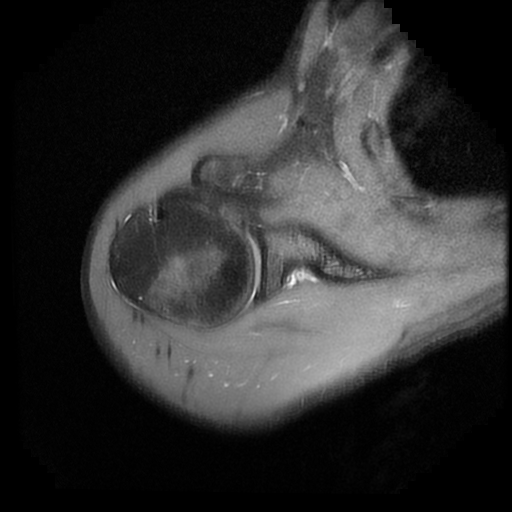

TECNICA EMPLEADA

Se coloca al paciente en decúbito supino, utilizando bobina dedicada de 8 canales, obteniendo imágenes en planos axial, sagital y coronal, secuencias, Spin Echo, Eco de Gradiente, potenciadas a Densidad de Protones, con pulsos de saturación de grasa.

HALLAZGOS IMAGENOLOGICOS

Lesión post traumática de Hill Sachs a nivel de la cabeza humeral, tendinosis aguda del supra espinoso.